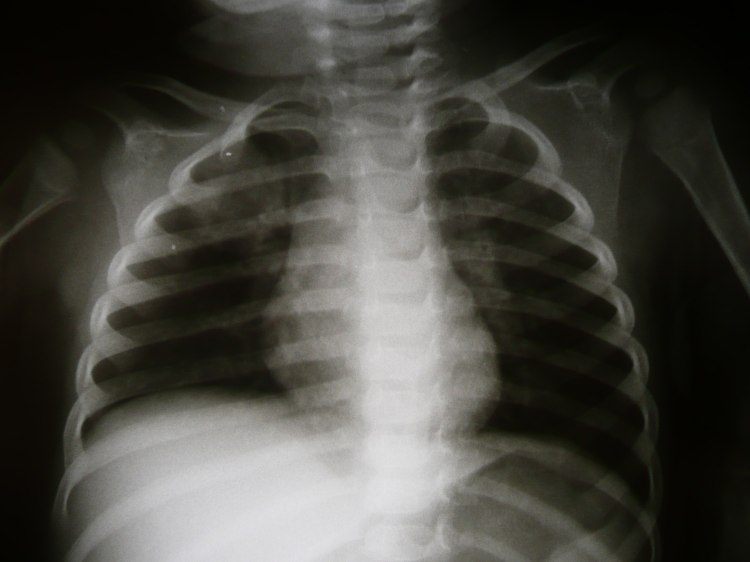

La radiografía de angiografía es una técnica de imagenología que se utiliza para visualizar los vasos sanguíneos del cuerpo. Esta técnica se utiliza para detectar problemas en los vasos sanguíneos, como obstrucciones, aneurismas y otras patologías.

File:Radiology 1300217.JPG - Wikimedia CommonsLa radiografía de angiografía se realiza mediante la administración de un contraste, que es un líquido que se inyecta en las venas o arterias del paciente. El contraste es visible en las imágenes radiográficas, lo que permite visualizar los vasos sanguíneos con claridad.